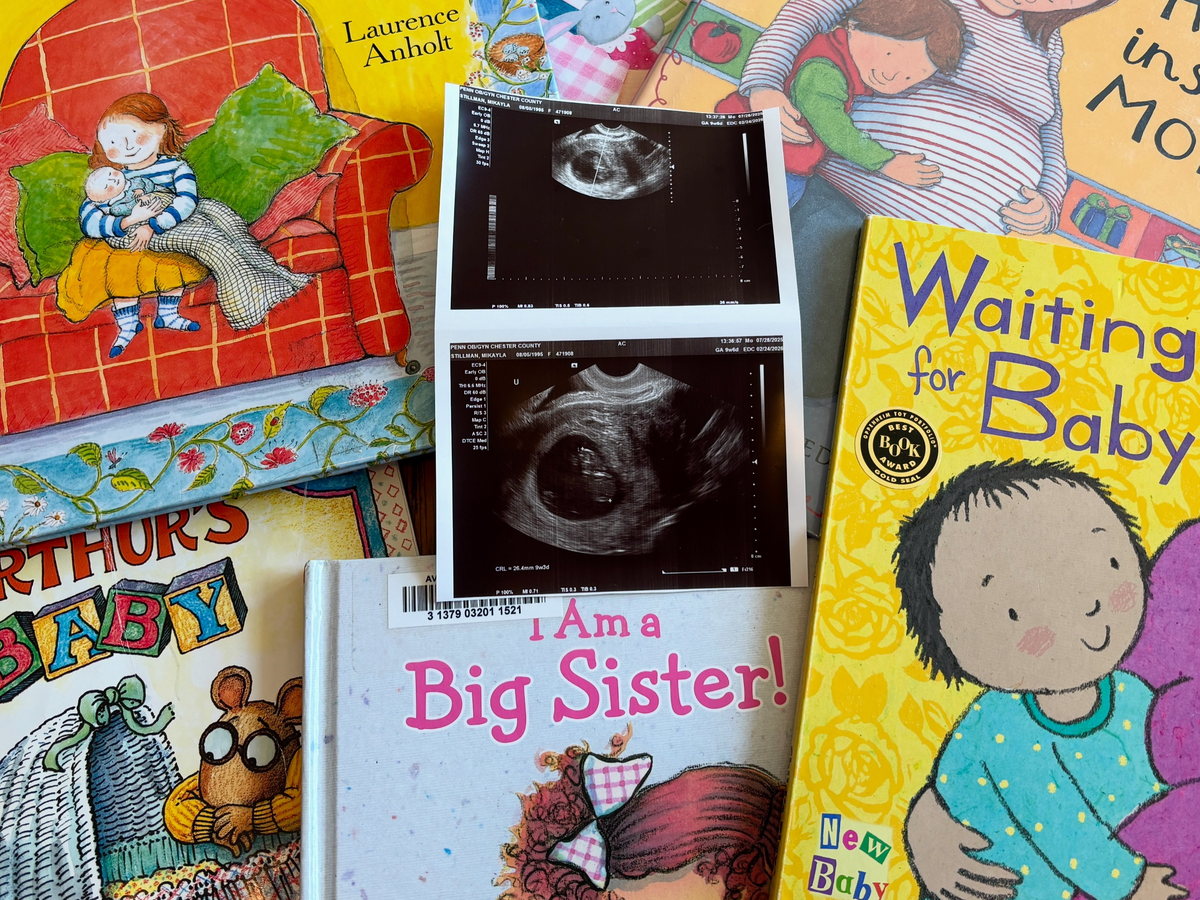

This pregnancy has been considered high-risk, which has meant many more medical appointments than we anticipated. Along the way, we’ve had a fetal echocardiogram to check Wyatt’s heart, extra growth scans, and twice-weekly non-stress tests, on top of regular prenatal care. While we are so grateful for attentive medical care, and grateful that Wyatt is healthy and expected to arrive within the next month, the costs have added up quickly.

Any funds raised through this GoFundMe will go directly toward current and future medical bills related to this pregnancy, the delivery, and welcoming baby Wyatt into the world.